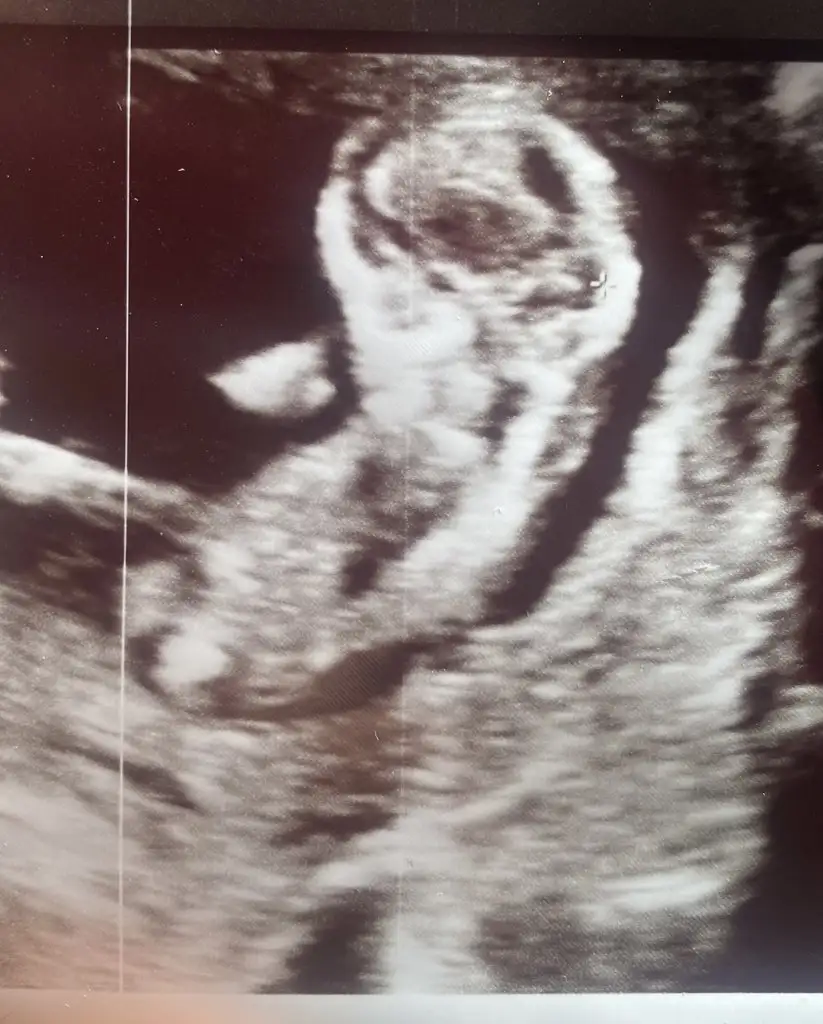

Güzel anneler merhaba perinatologum ile çok güzel geçti bugün, herşey yolunda çok şükür, ense pilisi, burun organlar vs veee oğluşumuz olacağını öğrendik, kolay kolay değişmez dedi